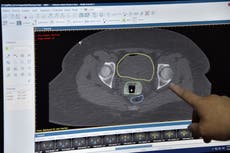

Le informaron que tenía cáncer de cuello uterino y, después de que se le hiciera una biopsia y se sometiera a varias exploraciones y una resonancia magnética, se reveló que tenía un tumor vascular de 6 cm en el cuello uterino, que requeriría tratamiento en lugar de cirugía para extirparlo.